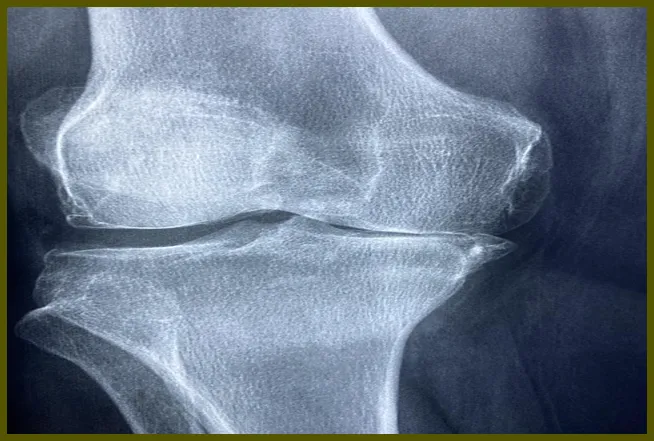

무릎 연골은 뼈와 뼈 사이에서 충격을 흡수하고 움직임을 원활하게 만드는 역할을 합니다. 이 연골이 손상되면 여러 가지 불편함을 초래하는데, 주로 무릎의 통증, 부기 및 운동 범위 제한 등이 발생합니다. 연골 손상은 일반적으로 외부 충격이나 과도한 운동에 의해 발생합니다. 예를 들어, 농구나 축구와 같은 스포츠에서 뛰거나 이동하는 과정에서 갑작스러운 움직임이 있으면 연골이 손상될 수 있습니다.

무릎 연골 손상의 증상

무릎 연골 손상은 여러 가지 증상을 동반합니다. 초기 증상은 미미할 수 있지만, 시간이 지나면서 점점 심해질 수 있습니다. 다음은 가장 흔한 연골 손상 증상입니다:

- 무릎 통증: 가장 흔하게 느껴지는 증상으로, 무릎을 움직일 때나 체중을 실을 때 더욱 두드러집니다.

- 부기: 무릎 주위에 부풀어 오르거나 붓는 현상은 무릎 부상을 나타내는 신호일 수 있습니다.

- 움직임 제한: 무릎의 운동 범위가 줄어들어 일상생활이 불편해질 수 있습니다.

- 소리: 무릎을 움직일 때 '딱딱' 소리가 나거나 '파삭'거리는 소리가 날 수 있습니다.